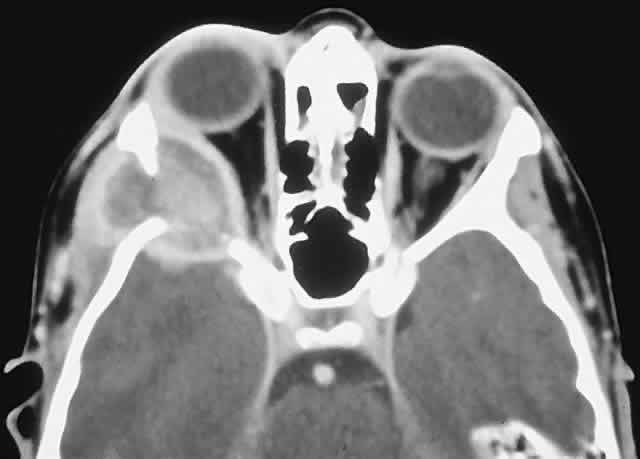

LANGERHANS CELL HISTIOCYTOSIS. Langerhans cell histiocytosis consists of a variety of syndromes resulting from the proliferation of Langerhans cells. Localized bone involvement (eosinophilic granuloma) is prevalent in boys ages 3 to 10 years. These children characteristically develop proptosis as a result of focal lytic superolateral lesions associated with soft tissue expansion.144–146 We have seen six cases of localized Langerhans cell histiocytosis, and each demonstrated a characteristic CT appearance of a central radiolucent area with an enhancing rim (Fig. 12). Histologically, there is a granulomatous and histiocytic infiltrate with Langerhans cells and prominent eosinophils.147 Localized periorbital disease is responsive to curettage, intralesional steroid injections, or low-dose radiation therapy. The prognosis is poorer in younger patients with visceral involvement.

Fig. 12. This 9-year-old boy had a 3-week history of right progressive proptosis associated with inward and downward displacement of the globe. CT demonstrated an osteolytic mass with an enhancing rim destroying the lateral orbital wall. Biopsy revealed Langerhans cell histiocytosis, and he was treated with surgical excision and intralesional steroids. He remains well after 5 years of follow-up. (Rootman J, Stewart BA, Goldberg RA: Orbital Surgery: A Conceptual Approach, p 45. Philadelphia: Lippincott-Raven, 1995.)